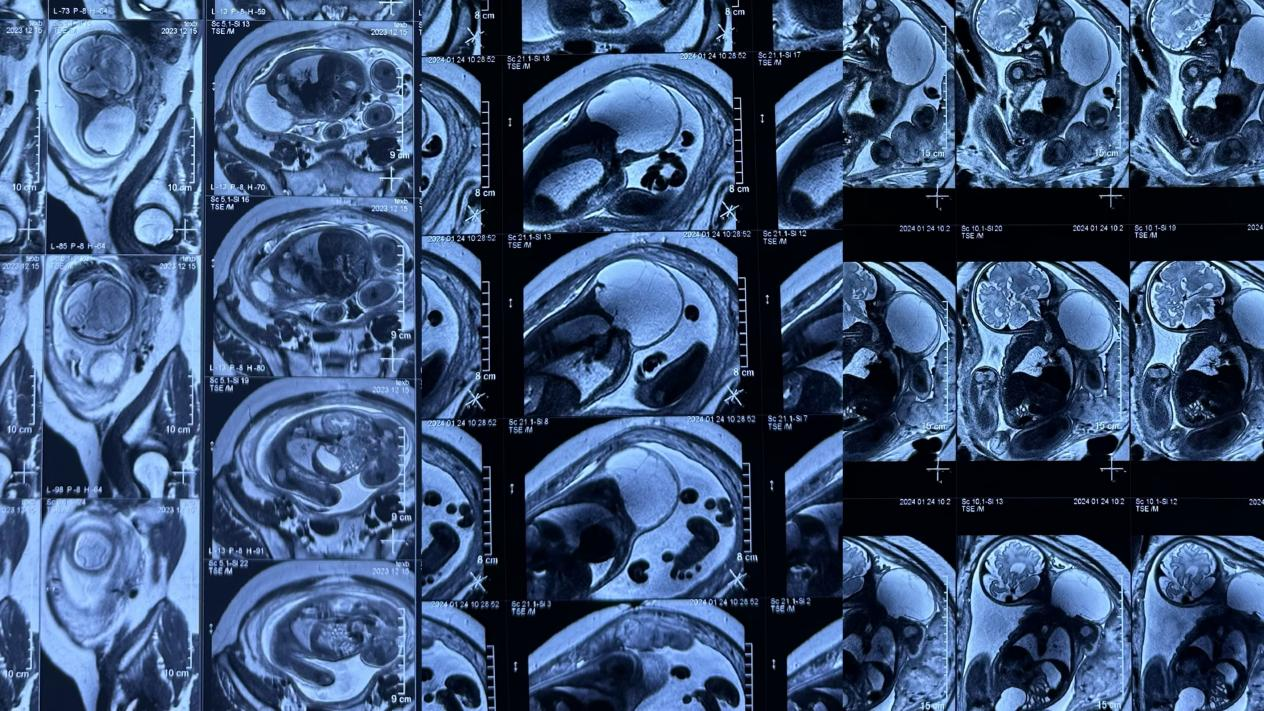

【辅助检查】1、超声检查提示无回声区,有分隔,呈囊状改变,CDFI:无血流信号,2、磁共振检查提示长T1长T2信号,囊状改变,压脂序列呈高信号,增强无明显强化。目的:1、超声检查用于明确诊断,2,磁共振检查用于了解淋巴管畸形病灶范围、侵及周围组织情况以及是否包绕重要器官如血管神经以及气管等。

胎儿淋巴管畸形磁共振检查

儿童淋巴管畸形磁共振检查